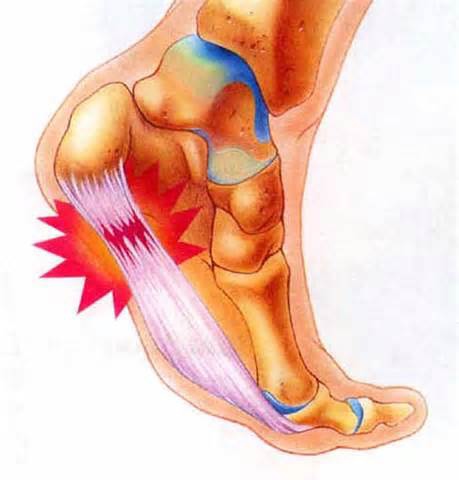

造成足底筋膜炎的原因 中壢高正雄骨科復健診所

足底筋膜炎手術 高正雄骨科復健診所